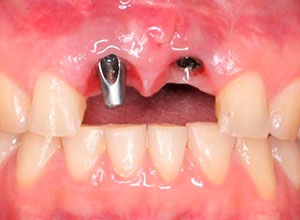

Paciente femenino a la cual le colocaron implante alto verticalmente, presentando a la vista una corona con un excedente de aproximadamente 5 milímetros, de porcelana rosa.

La paciente inconforme con los resultados nos visita, realizamos estudios radiográficos y tomográficos, encontrando que se perdió hueso verticalmente en el implante.

Decidimos hacer una corticotomia alveolar, dejando tejidos blandos en su lugar y cambiar la corona de cerámica por una corona de acrílico para cementar bien los brackets y poder empezar con la distracción.

Después de la corticotomia dejamos un tiempo de siete días para que se organizaran las células tisulares.

Se empezó a hacer la distracción, primero con un arco recto y posteriormente con elásticos haciendo el recorte con el borde incisal conforme se va bajando el implante con el bloque óseo.